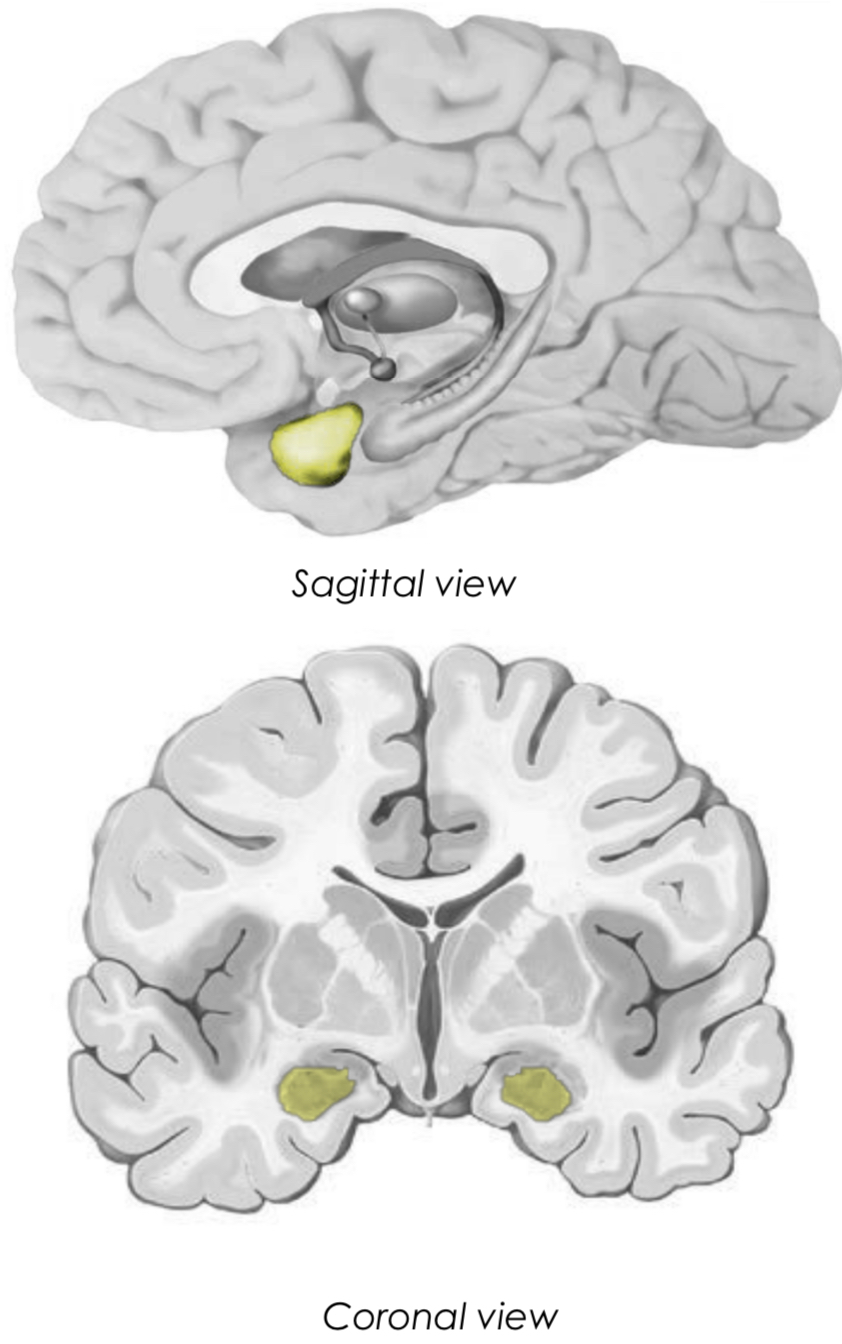

What is the amygdala?

Where is it found and what is its main function?

It is an almond shaped nuclear complex (collection of cell bodies) in the medial temporal lobe

it is located deep to the uncus

it is mainly involved in emotions and behaviour

What is the primitive role of the amygdala?

How can we control this?

The primitive role is important for species preservation

e.g. feeding, drinking, sex, nurturing, need for survival

we have control of the amygdala due to the neocortex allowing us to rationalise and acquire context, whereas animals do not